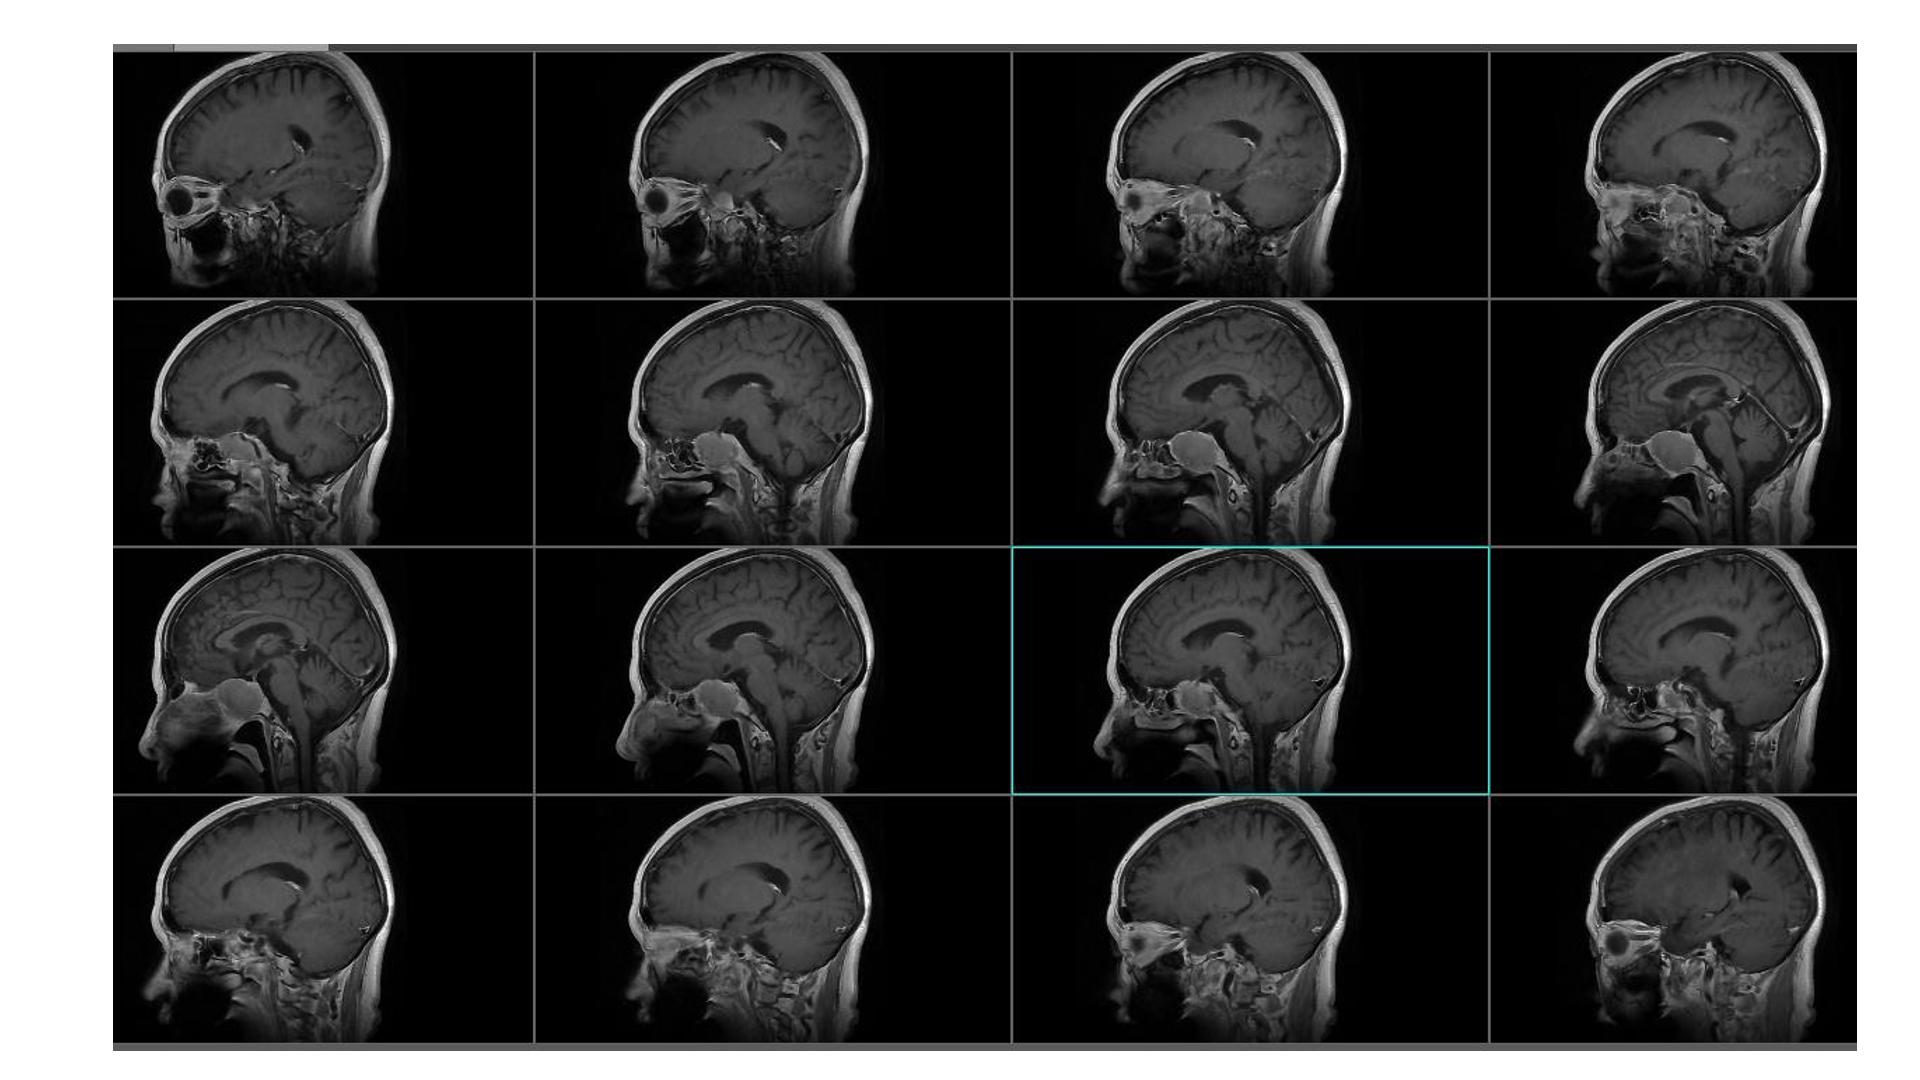

鞍区占位,蝶鞍扩大明显,侵袭海绵窦。